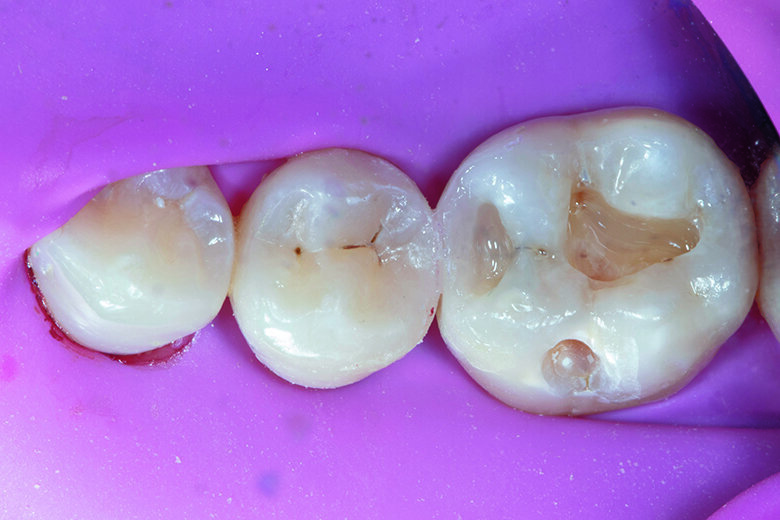

A 21-year-old female visited the dental office with a chief complaint of food lodgment and pain in tooth #46 when consuming sweet or cold food. Radiographic examination with IOPA reveled old composite restoration in tooth #46 and distal decay on #45 without involving the marginal ridge. Upon clinical examination, Class II cavities on tooth #46 & #45 were identified (Fig. 1). The most suitable treatment approach in this situation was direct restorations with bioactive composite resins.

Fig. 1. MO Class II cavity along with old composite restoration on tooth #46 and distal decay on tooth #45.